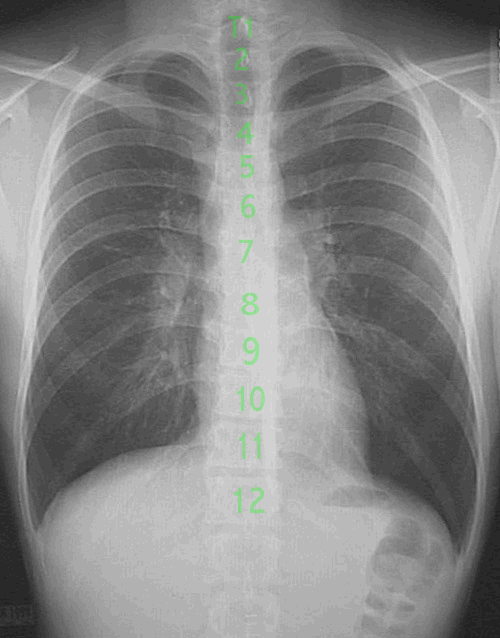

Each of the 12 thoracic vertebrae are attached to a pair of ribs. This part of the skeleton houses almost all of the vital organs. The ribs serve as a bony cage for protection of the delicate organs. Unlike the cervical spine, the thoracic spine is flanked on both rear sides by additional bones that provide protection. The rear sides have additional protection via the scapulae, or shoulder blades. These are thick, dense bones that serve as additional protection as well as an attachment for many muscles. The attachment of muscles provide leverage points for muscular contraction which allows us to move our arms freely. Without the shoulder blades, we would have very limited motion of the arms because muscles such as the trapezius, teres minor, teres major, supraspinatus, infraspinatus, levator scapula, latissimus dorsi, serratus anterior, rhomboids and others would not have complete attachments and could not contract fully.

The thorax, or the area between the first and twelfth thoracic vertebrae, consists of 24 ribs, 2 clavicles, 2 scapula, 12 vertebrae and the sternum. Of all of these bones, the scapula has the greatest freedom of movement. It's only articulation is at the shoulder where it forms the glenohumeral joint and the acromioclavicular joint. Since the shoulder does not form a joint near the middle, it has less natural restriction in movement. Therefore, the position of the scapula can vary greatly. However, we can assess some common reference points with a person in a neutral, relaxed position.

The scapula is a triangular shaped bone on the rear portion of the thorax. It overlies the rib cage and covers parts of the 2nd to 7th ribs. It connects the clavicle, or collarbone, to the upper arm. This forms the shoulder girdle. The shoulder joint has the greatest freedom of motion of any joint in the human body. This freedom of movement comes at the expense of the joint's laxity and instability.

In an anatomically neutral position, portions of the scapula can be related to other bony parts of the body. The superior angle of the scapula is commonly found at the level of the 2nd thoracic vertebra. The inferior angle of the scapula is located adjacent to the spinous process of the seventh thoracic vertebra (Clinically Oriented Anatomy, 3rd Ed., Keith L. Moore) The acromion process is commonly located within the T1-T2 level (Atlas of Human Anatomy, Frank M. Netter, MD). This bony prominence can vary position depending upon the level of muscular contraction of the trapezius and levator scapula. If minimally contracted, the acromion may be found slightly higher than T1. You can see this by shrugging your own shoulders.